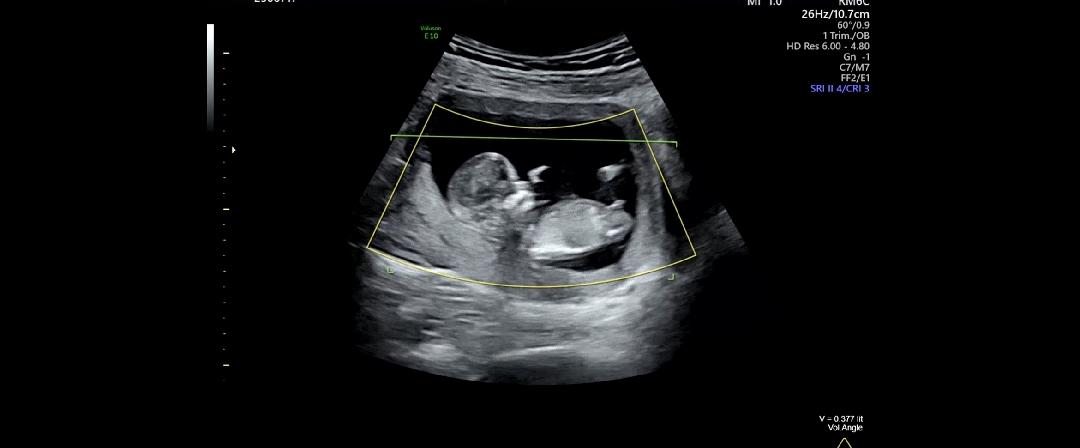

각도법 성별 봐주세요ㅎㅎ!

딸일까요? 아들일까요?